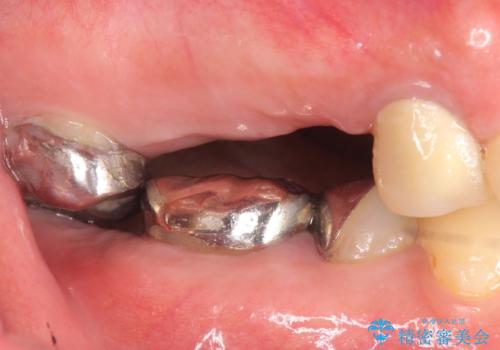

- 右上のブリッジでものを咬むと違和感があり、歯茎に膿の出口もできているので診て欲しいといらっしゃった方の症例です。

右上の567ブリッジを外したところ、右上5は歯根破折により保存不可能だったため、右上56部にインプラントを埋入し欠損補綴を行いました。